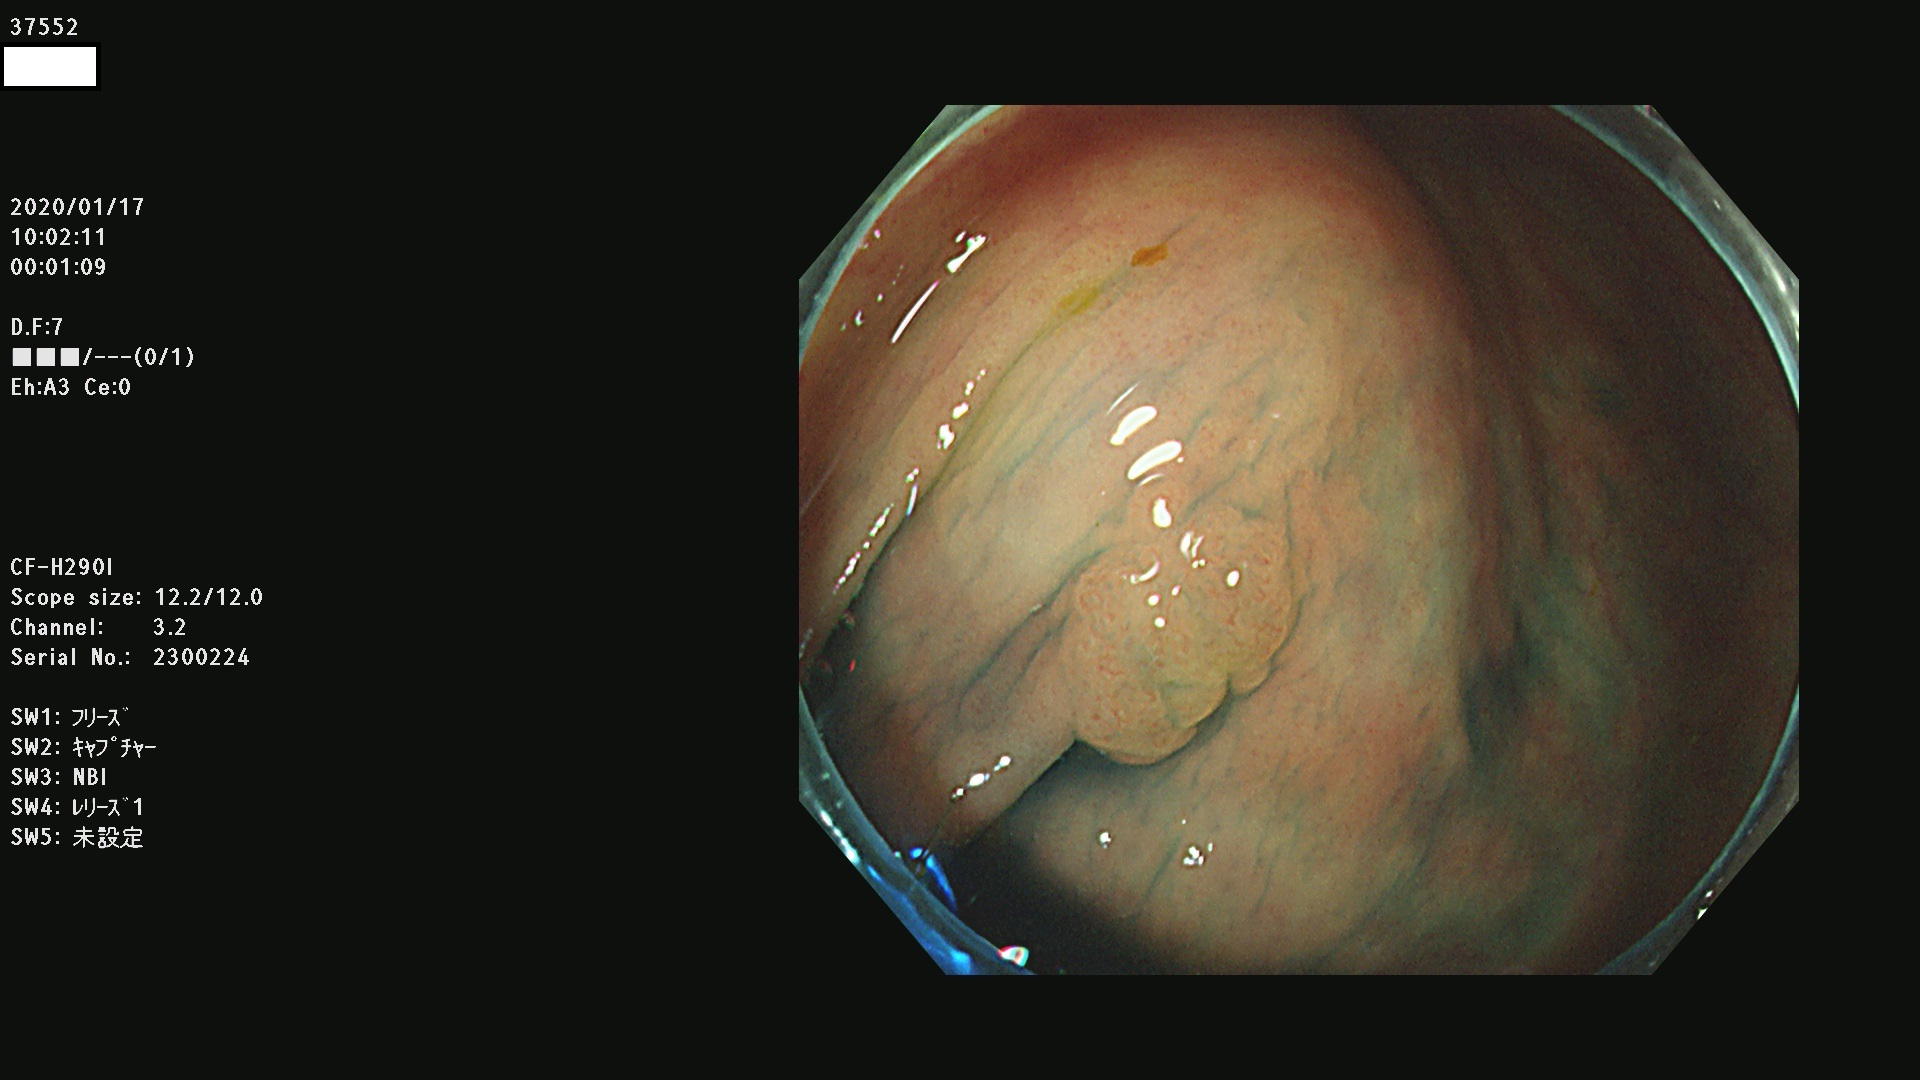

発見困難で危険性の高い平坦型病変(上記100名より抽出) ![]()